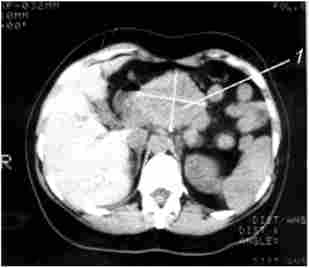

Комп'ютерна томографія. Рак тіла підшлункової залози

Мал. 213. Комп'ютерна томографія. Рак тіла підшлункової залози:

1 - гіподенсная пухлина тіла підшлункової залози з нерівними горбистими контурами 6x6 см